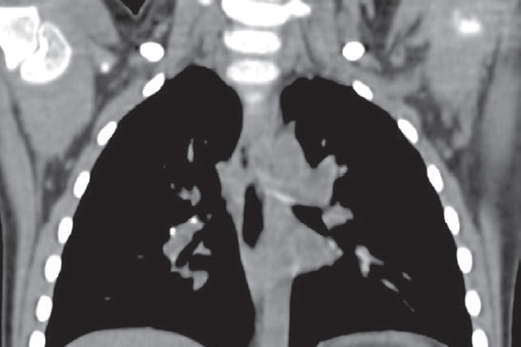

Клинический пример 1. Девочка Л., 3 года, привита БЦЖ в роддоме. По динамике проб инфицирована с гиперергией по ПМ (папула — 18 мм) и выраженной реакцией на ДСТ (папула — 14 мм). При поступлении в стационар отмечались признаки ринофарингита, бронхита. Симптомы интоксикации были выражены умеренно и носили смешанный характер, температура тела нормальная. В клиническом анализе крови лейкоцитоз (14,9 ∙ 109/л) с нейтрофильным сдвигом, ускорение СОЭ (23 мм/ч). На обзорной рентгенограмме — полная норма. Проведена неспецифическая антибактериальная терапия в течение 10 дней — катаральные симптомы купированы. Учитывая эпиданамнез, положительную пробу с ДСТ, выполнена КТ грудной клетки с внутривенным контрастированием — обнаружены единичные кальцинаты в бронхопульмональной группе лимфоузлов справа (рис. 5). Установлен диагноз: «Туберкулез внутригрудных лимфоузлов бронхопульмональной группы справа в фазе неполной кальцинации, МБТ(–)».

Рис. 5. Компьютерная томография грудной клетки девочки Л., три года (туберкулез внутригрудных лимфоузлов)

Fig. 5. Chest computed tomography scan of the 3-years old girl (intrathoracic lymph node tuberculosis)